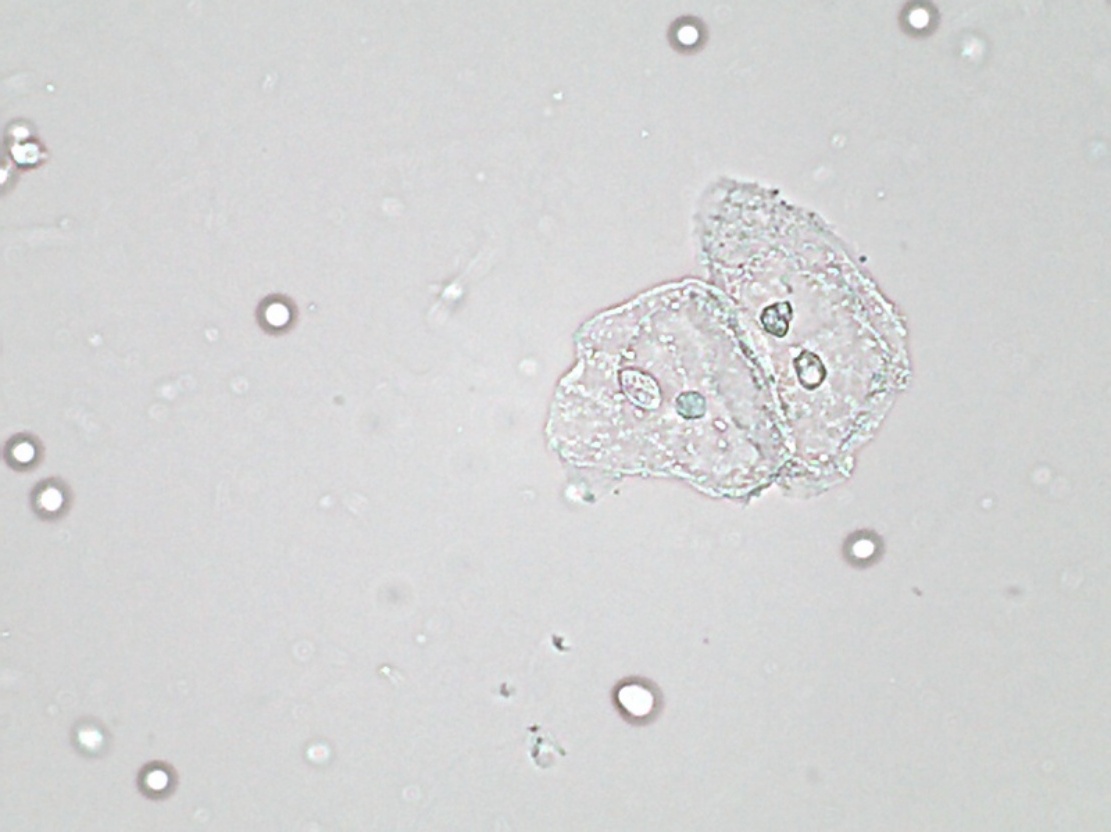

(a) annotations

Refer to caption

(b) ZF

(c) VGG-16

(d) ResNet-50

(e) PVANet

(f) SSD300

\Romannum5 : detection results of epithelial nuclei

Figure 8: Selected detection examples of urine particles on urinalysis test set. We show detections with scores higher than 0.7. All examples are divided into 7 groups, where 5 groups are at high-power field (i.e., erythrocyte, leukocyte, crystal, mycete, epithelial nuclei ) and the other 2 groups at low-power field (i.e., epithelial cell, cast ). In each group: (a) shows original image with ground truth boxes; (b-d) are Faster R-CNN detections separately on ZF, VGG-16 and ResNet-50 networks with a anchor scales of {322,642,1282,2562,5122}superscript322superscript642superscript1282superscript2562superscript5122\{32^{2},~{}64^{2},~{}128^{2},~{}256^{2},~{}512^{2}\}; (e) shows detection results on PVANet; (f) shows detection results on SSD300 model. For the ground truths and detection boxes, different categories use only different colors: eryth (red), leuko (black), epith (green), crystal (magenta), cast (cyan), mycete (yellow). As shown in this figure, the performance of SSD is inferior to Faster R-CNN, and it misses a lot of small objects.